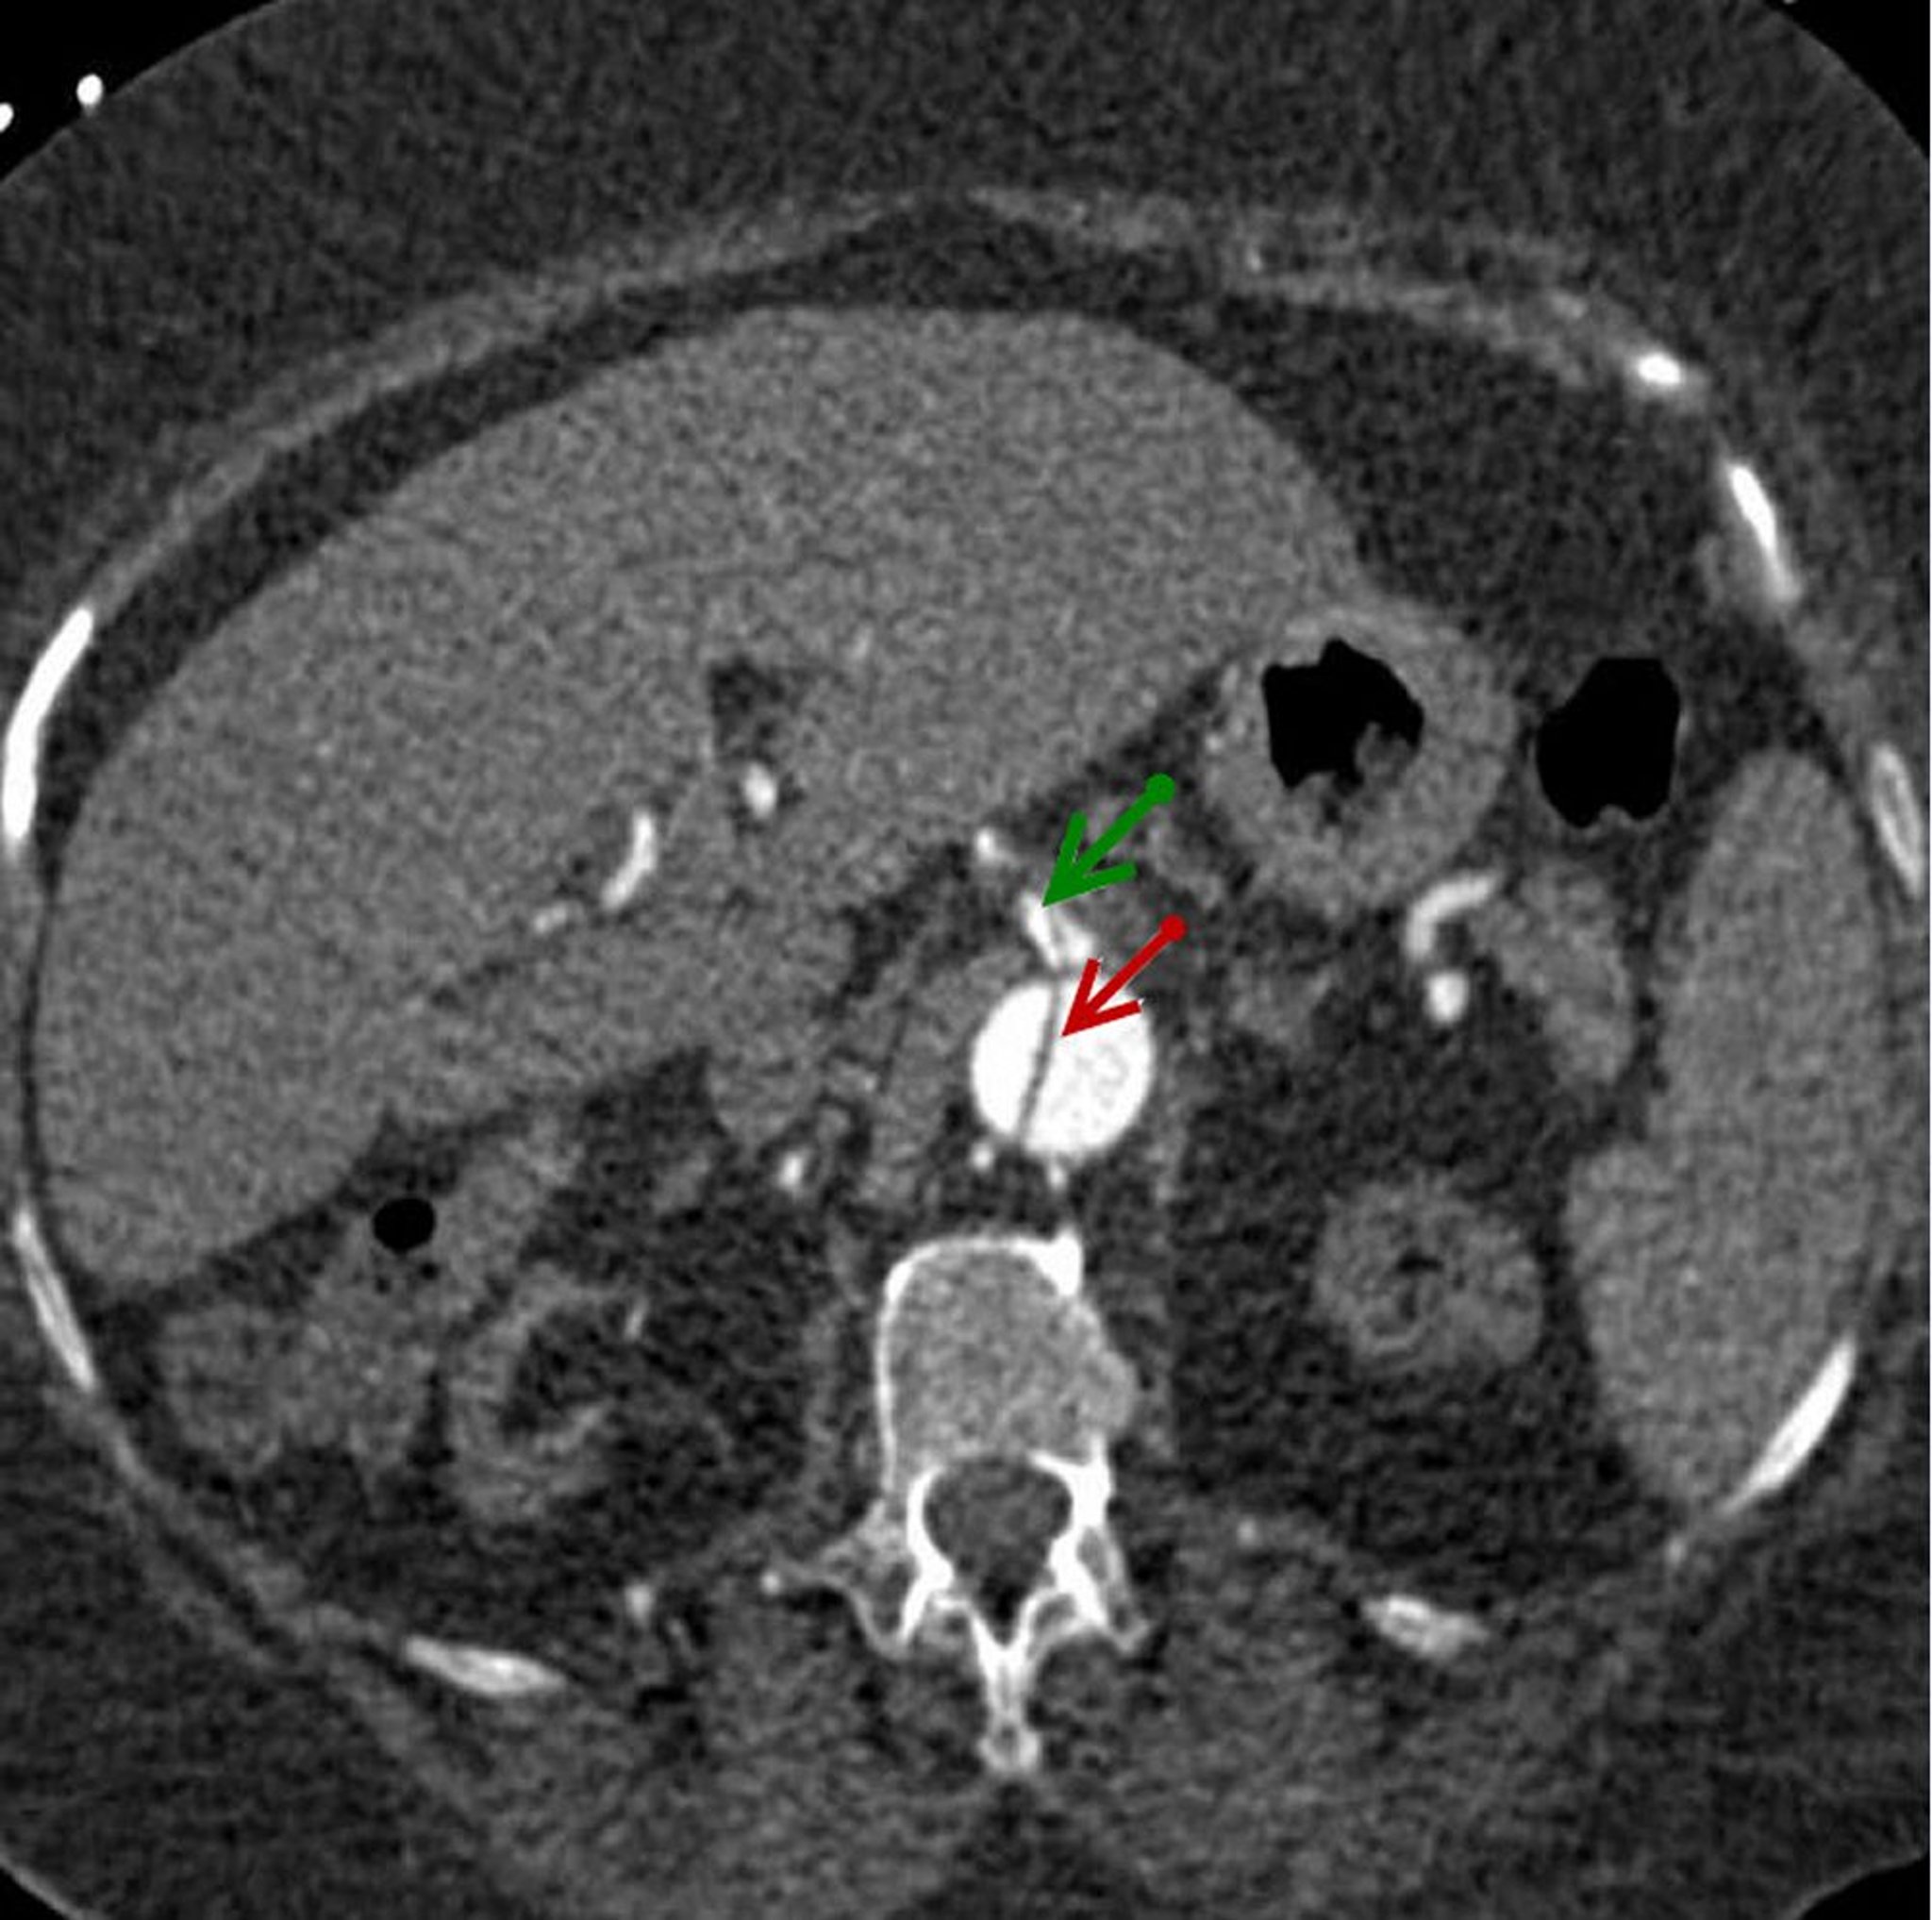

腹部大動脈解離

上腸間膜動脈(緑矢印)に進展している腹部大動脈(赤矢印)の解離したフラップの水平断像。

© 2017 Elliot K.Fishman, MD.